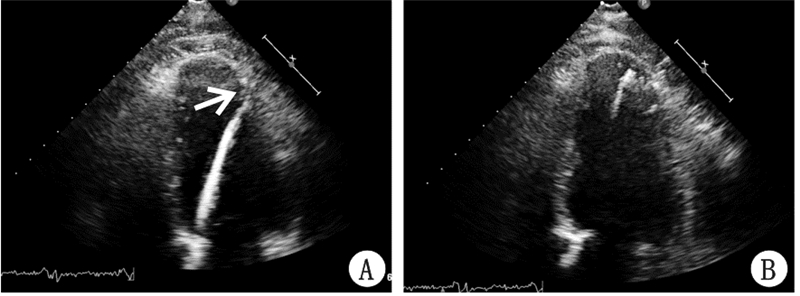

经胸超声心动图监测3例患者中2例伞叶足位于左心尖,指引导管和心脏长轴一致。1例伞叶足靠近左室下壁中下段(图 1A),在经胸超声心动图直视下进行及时调整后指引导管和心脏长轴保持一致(图 1B)。术中猪尾导管造影及超声心动图监测均提示封堵器位置固定良好。2例左心声学造影于左室显影即刻未发现室壁瘤内造影剂信号(图 2A),彩色多普勒检查未探及伞周血流;1例左心声学造影于左室显影即刻室壁瘤内可见少许造影剂信号(图 2B),彩色多普勒检查探及伞周少许残余血流信号(图 3A)。3例彩色多普勒检查Parachute伞叶均可见快闪伪像(图 3B)。

| A:箭头示指引导管先端靠近左室下壁中下段;B:指引导管和心脏长轴一致、先端位于左心尖 图 1 超声心动图监测指引导管位置 |